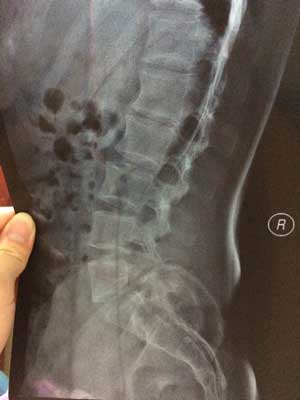

(图:于先生检查时的x光片,蒙兴文主任诊断为强直早中期)

CT检查:腰椎正侧位片及双侧骶髂关节正位片示,腰椎无异常,双侧骶髂关节间隙无变化,骶髂关节骨质密度增高,边缘模糊,局部有虫蚀样改变。较终确定患上强直性脊柱炎,已发展至早中期。